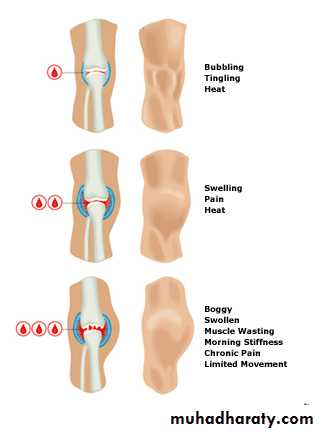

What happens in a joint bleed?

joint feels tingly and warm.Swelling, painful and difficult to move.

Long-term effects of Joint bleeds?

Repeated bleeding causes synovium (lining) to swell

The synovium stops producing the slippery, oily fluid that helps the joint move.

Damages the cartilage- joint stiff, painful and unstable.With time, most of the cartilage breaks down and some bone wears away. The whole process is called haemophilic arthropathy.